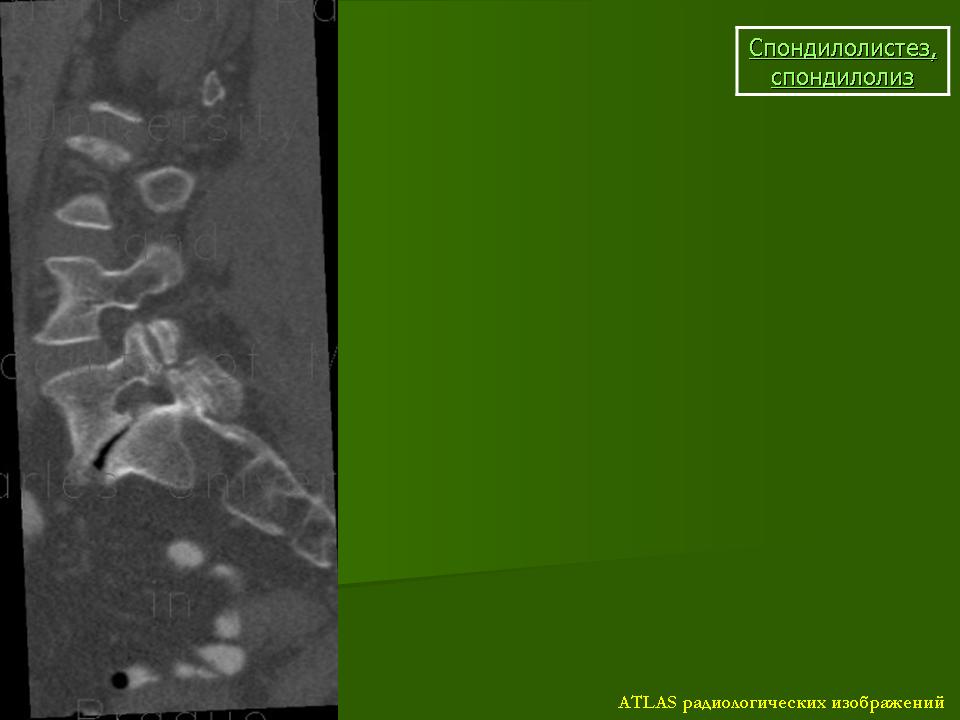

Рис.3a,b,c. Истмический спондилолистез (спондилолиз). a) Рентгенограмма поясничного отдела позвоночника. Стрелкой указана зона дефекта (спондилолиза) дужки L5 позвонка. b) Компьютерная томограмма (КТ) L5 позвонка. Стрелкой указана зона дефекта (спондилолиза) дужки L5 позвонка. с) Магнитно-резонансная томографи (МРТ) поясничного отдела позвоночника. Стрелкой указано смещение L5 позвонка кзади I степени.